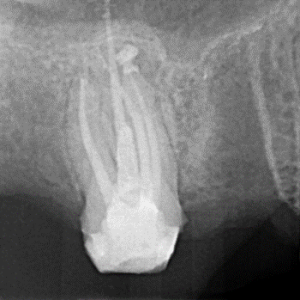

Clinical Cases